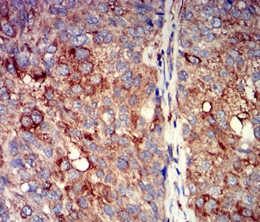

IHC    1/100 - 1/500